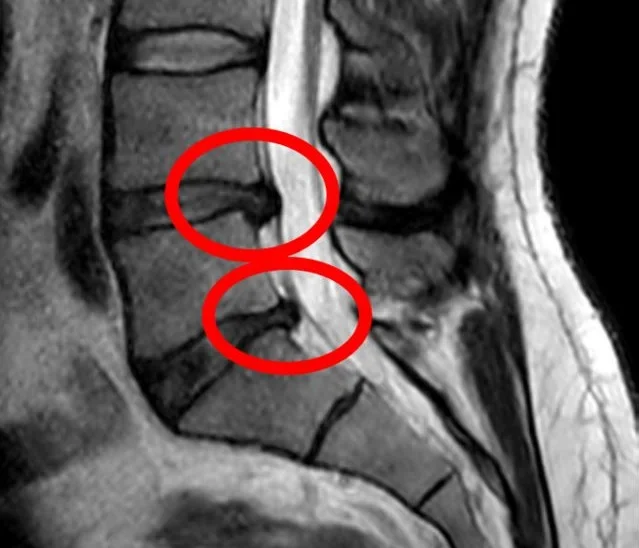

MRI Scan

MRI is considered the most accurate imaging technique for diagnosing cervical disc herniation.

It clearly shows:

- disc bulging or protrusion

- nerve root compression

- spinal cord involvement